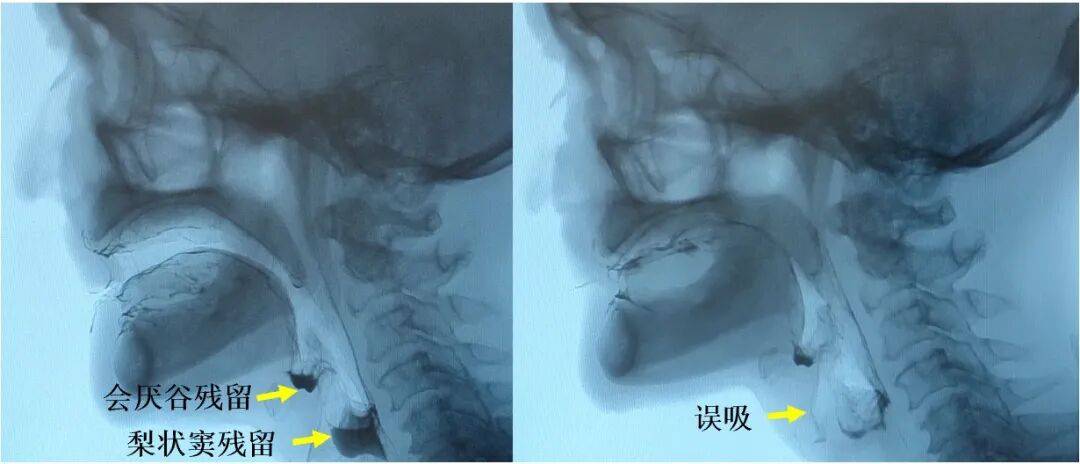

咽缩肌的病理组织改变的减轻最终在功能效应层面表现为咽缩肌功能的显著改善。造影检查显示,对比标准放疗组,内侧组咽后区豁免放疗组中出现会厌谷残留(74% vs. 100%;P<0.001)、梨状窦残留(48% vs. 73%;P=0.01)、咽后壁残留(11% vs. 27%;P=0.01)、咽通过时间>1.0秒(2% vs. 11%;P=0.03)及误吸(12% vs. 29%;P=0.03)等咽期受损表现的频率均更低。

图4:造影检查所示会厌谷残留、梨状窦残留及误吸